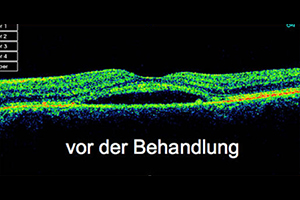

Beispiel: Feuchte altersbedingte Makuladegeneration

68-jähriger Patient mit zunehmender Sehminderung seit 6 Wochen auf 0,3 (30%). Nach 3-maliger Anti-VEGF Therapie Rückgang des Ödems und Besserung auf 0,5

vor der Behandlung